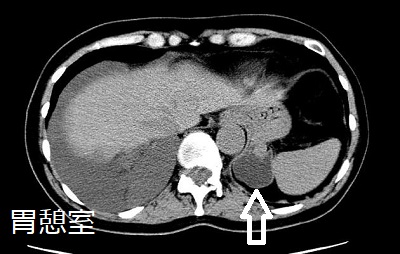

左副腎偶発腫瘍(インシデンタローマ)に見えても、実は胃憩室(gastric diverticulum)の事があります。胃憩室は、胃壁の一部が袋状に拡張し、突出したものです。他の消化管憩室に比べて頻度が低く、甲状腺専門医が遭遇する機会は、ほとんどありません。(表;Qlifeより)

胃憩室は胃穹窿部に好発し、CTにおいて

- 左副腎近傍に位置する

- 内部は胃液なので低吸収(CT値が10HU未満)→左副腎腺腫と鑑別

- 内部にガスを含んでいるか、胃との連続性を確認できれば診断は容易

確定診断として、胃内視鏡もしくは上部消化管造影における憩室(バリウムの貯留)の確認